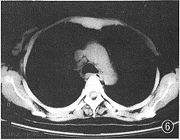

图6 AIDS合并肺结核,4R区淋巴结肿大

2.纵隔淋巴结肿大:1例。X线胸片见右上纵隔阴影增宽。胸部CT见2R、4R及7区淋巴结肿大,淋巴结最大直径为2 cm(图6)。